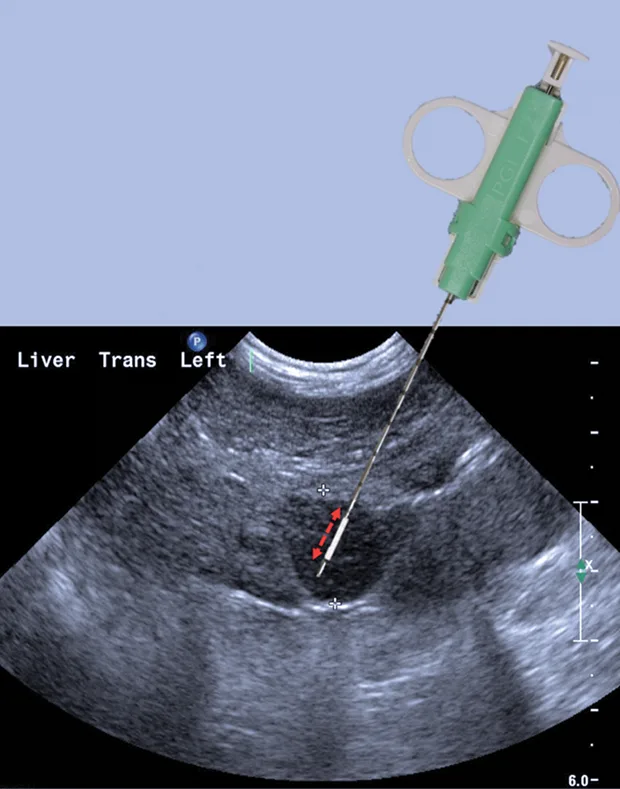

Biopsy needle tract within the patient after firing and just before removing the biopsy device (B). Post-biopsy hemorrhage often collects between hepatic lobes as seen in this image (white arrow heads) (C). The echogenic fluid represents acute hemorrhage. Color flow Doppler post-biopsy ensures there is no persistent hemorrhage in the peritoneal space (D). Power Doppler imaging is the most sensitive form of Doppler to detect the presence or absence of blood flow.

Step 4: Plan the Trajectory

There are 4 key steps to ensure proper needle placement. First, the needle should always be oriented with the long axis of the transducer to ensure needle visualization throughout its length and through the entire process. Always know where the tip of the needle is. The second step is to realize the transducer's orientation to anticipate from which direction of the monitor the needle will enter. In general, enter from the same side of the transducer (transducer notch) for biopsies and fine-needle aspirates (5B). Anticipate exactly where the needle tip will enter the patient relative to the transducer to visualize the tip immediately on the screen. Third, the angle of trajectory should be calculated based on the depth of the lesion. Deeper lesions require a steeper angle, and superficial lesions require shallow angles. Once the angle is planned, place the needle approximately 1 cm away from the head of the transducer, oriented in planned trajectory. Do not go perpendicular to the skin if the transducer is placed perpendicular to the skin, as the parallel configuration is the worst possible reflector, and the biopsy device will not be seen in the image. Make a small skin incision with a No. 11 blade to facilitate needle placement.

Step 5: Advance Needle

Preload the biopsy device before advancing in the tissue. Advance the needle to the near field and pick up the needle device in the scan plan. Then, advance the biopsy needle tip to the area of interest or focal lesion. Next, move the transducer to find the needle tip (ie, do not move the needle to find the transducer) and reassess trajectory. With the trajectory planned and the needle 1 cm away from the transducer, the needle can be advanced for a semiautomated device before firing the outer cutting sleeve. Visualize the needle throughout the entire process to ensure proper sampling of the lesion selected and avoid inadvertent needle placement.